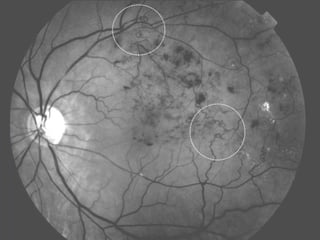

Les occlusions veineuses rétiniennes (OVR) touchent entre 6.000 et 60.000 nouveaux patients par an, avec un âge moyen de diagnostic de 57 ans pour les OVR et 65 ans pour les autres formes. Les causes et l'évolution de la maladie sont souvent imprévisibles, avec des traitements divers allant des médicaments à la chirurgie, mais les complications comme l'œdème maculaire demeurent fréquentes. Les traitements potentiels comme les injections intra-vitréennes peuvent entraîner des effets indésirables, dont un risque accru de cataracte.